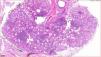

HistopathologyHistopathology showed lymphoid clusters consisting mainly of plasma cells with a periglandular distribution (Fig. 2). Immunohistochemistry was positive for CD20 and negative for IgG and IgG4, and revealed monoclonal λ light chains but was negative for κ light chains (Fig. 3).

Histologically, features that suggest benignity include preserved acinar architecture and the presence of small lymphocytes and plasma cells in the interfollicular regions with a nondiffuse pattern distinct from that of lymphoproliferative infiltrate.4